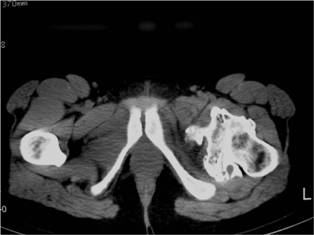

CT

- The cap will appear as soft tissue with calcification

- Can be difficult to distinguish from muscle